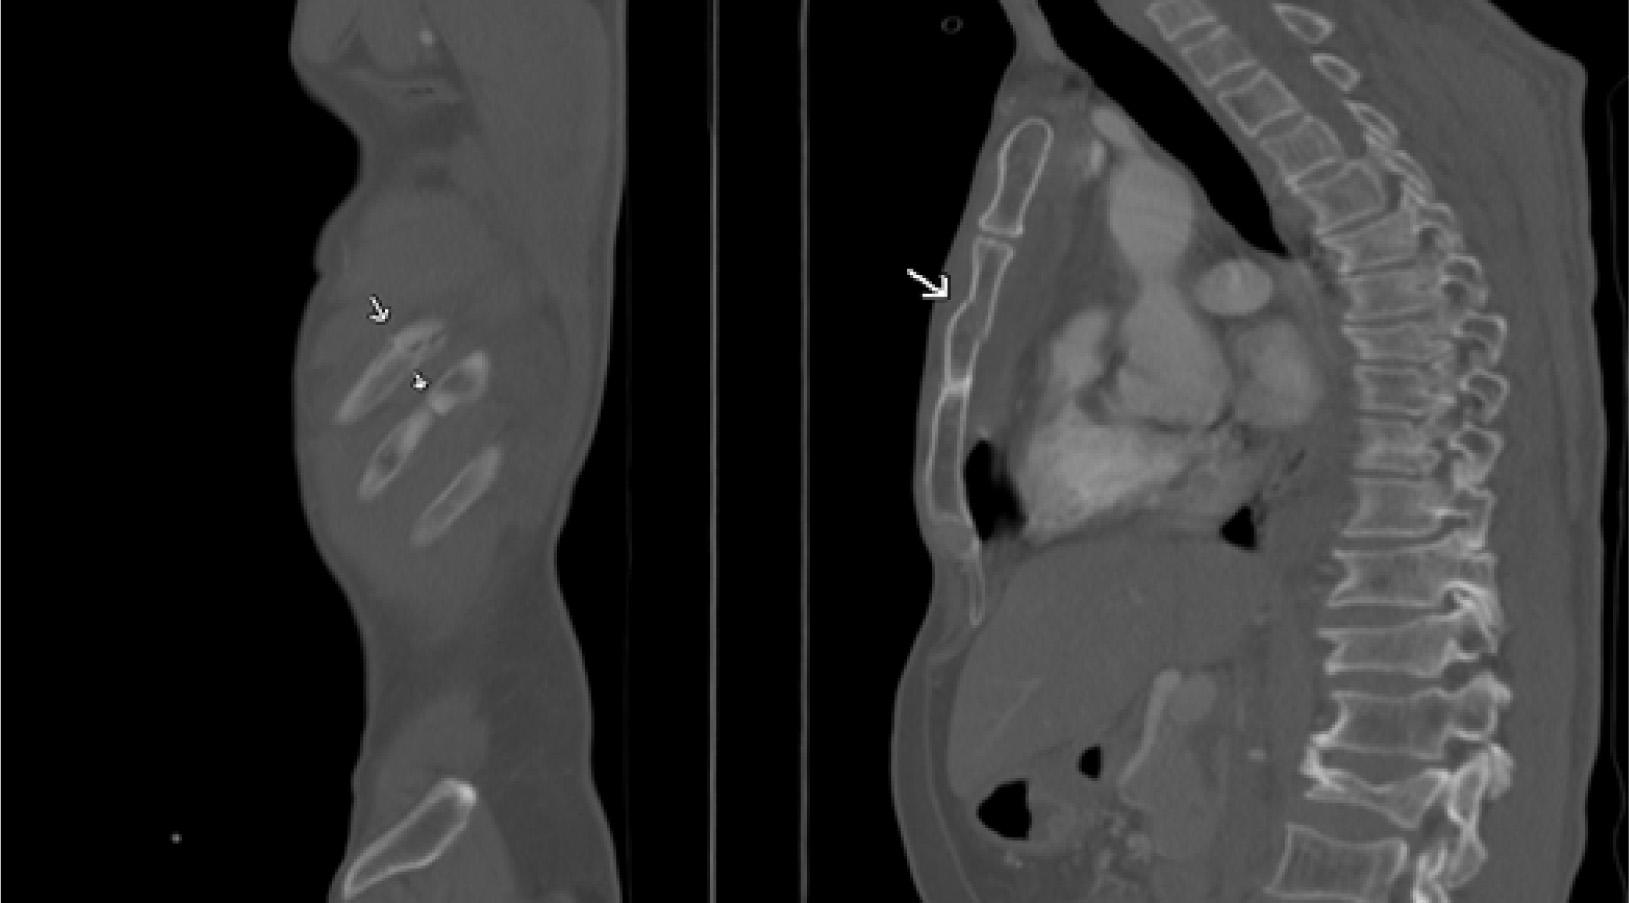

Figure 1